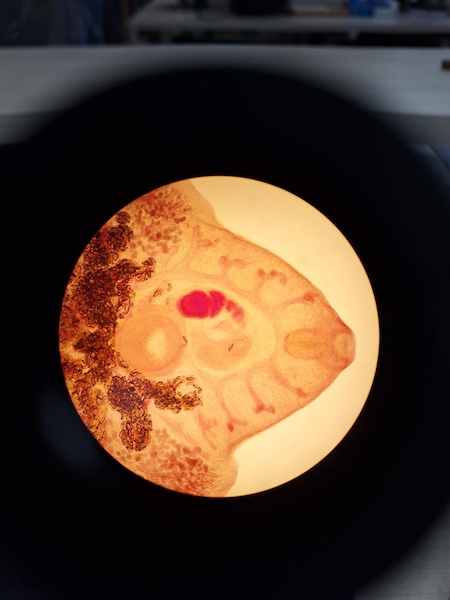

Dzień rozpoczął od samodzielnego badania preparatów parazytologicznych, następnie analizował różnorodne materiały naukowe. Otrzymał również propozycję wykonania sekcji glisty ludzkiej oraz tasiemca uzbrojonego, które zaplanowane zostały na kolejną wizytę.